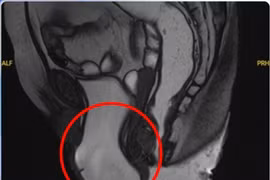

Khối sa sàn chậu đã được xử lý triệt để, không còn gây cản trở trong sinh hoạt, đồng thời tình trạng rối loạn tiểu tiện cải thiện rõ rệt so với trước mổ.